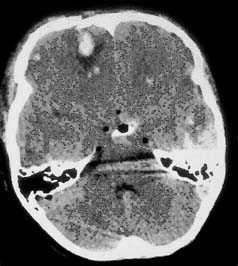

б - Изолированное кровоизлияние в ствол мозга (стрелка) у 12-летней девочки, ШКГ 3 балла. Примечание: травму ствола мозга лучше всего диагностировать с помощью МРТ. а - Кровоизлияние в таламус (стрелка) у молодого пациента, поступившего в глубокой коме (ШКГ 4 балла).

б - Пневмоцефалия у пожилого пациента с лобно-базальной травмой. а - Вклинение под серп мозга (одна стрелка), вызывающие гидроцефальное расширение контралатерального желудочка (двойная стрелка) из-за большой острой субдуральной гематомы.

б - Транстенториальное вклинение среднебазального отдела височной доли, вызванное большой острой субдуральной гематомой. Типичная КТ больного с вклинением миндалин мозжечка а - Диффузный супратенториальный отек головного мозга у маленького ребенка.